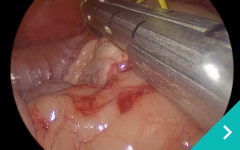

腹腔鏡手術は、この開腹手術の課題である患者さんの負担を軽減させるため、小さな傷口3つほどをあけ、胃や腸がある腹腔にCO2ガスを注入して膨らませてから内視鏡カメラやメスなどを挿入して手術する方法です。

ミニマム創内視鏡下手術は腹腔鏡だけでは対処ができないような手術の際に、お腹にラッププロテクターという器具を設置して行う腹腔鏡と開腹手術を組み合わせた手術です。